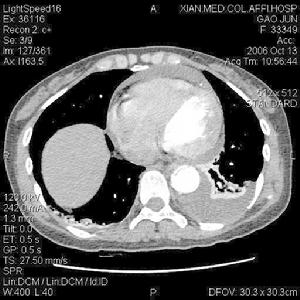

4.CT與MRI檢查CT檢查對心包增厚具有相當高的特異性和分辨力,可評估心包的形狀及心臟大血管的形態,如腔靜脈擴張、左室後壁纖維化及肥厚等,是對可疑的縮窄性心包炎有價值的檢測手段。MRI可清楚顯示縮窄性心包炎的特徵性改變即心包增厚,能準確測量其厚度,判斷其累及範圍,並能顯示心臟舒張功能受限所引起的心臟大血管形態及內徑的異常改變,如右室流出道狹窄及肝靜脈、下腔靜脈擴張等。